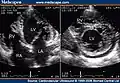

-

Two-dimensional apical four chamber and parasternal short axis images at the level of the ventricles show dilatation of both ventricles, multiple trabeculae and intertrabecular recesses in inferior, lateral, anterior walls, middle and apical portions of the septum and apex of the left ventricle. [1] -

Transthoracic two-dimensional echocardiogram in apical four chamber and parasternal short axis at the level of both ventricles demonstrate dilatation, deep trabeculae and intertrabecular recesses in the inferior, lateral, anterior walls, middle and apical portions of the septum and apex of the left ventricle. [3] -